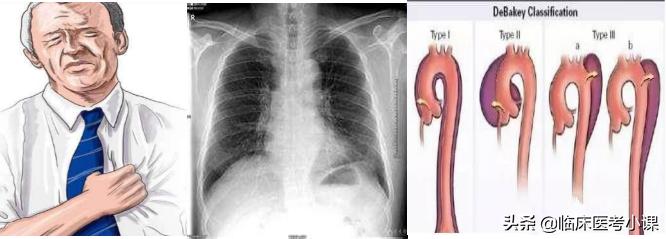

心绞痛 胸膜炎 夹层动脉瘤

心血管疾病:冠心病、心肌病、肺梗死、夹层动脉瘤等

带状疱疹 :成簇的水泡沿着一侧肋间神经分布伴剧痛, 疱疹一般不超过体表中线。

心绞痛心肌梗塞 :多在胸骨后方、心前区或剑突下, 为压榨样疼痛,可向左肩和左臂内侧放射,可达无名 指与小指。

夹层动脉瘤 :多位于胸背部,向下放射至下腹、腰背 部与两侧腹股沟和下肢。

胸膜炎 :多在胸侧部。